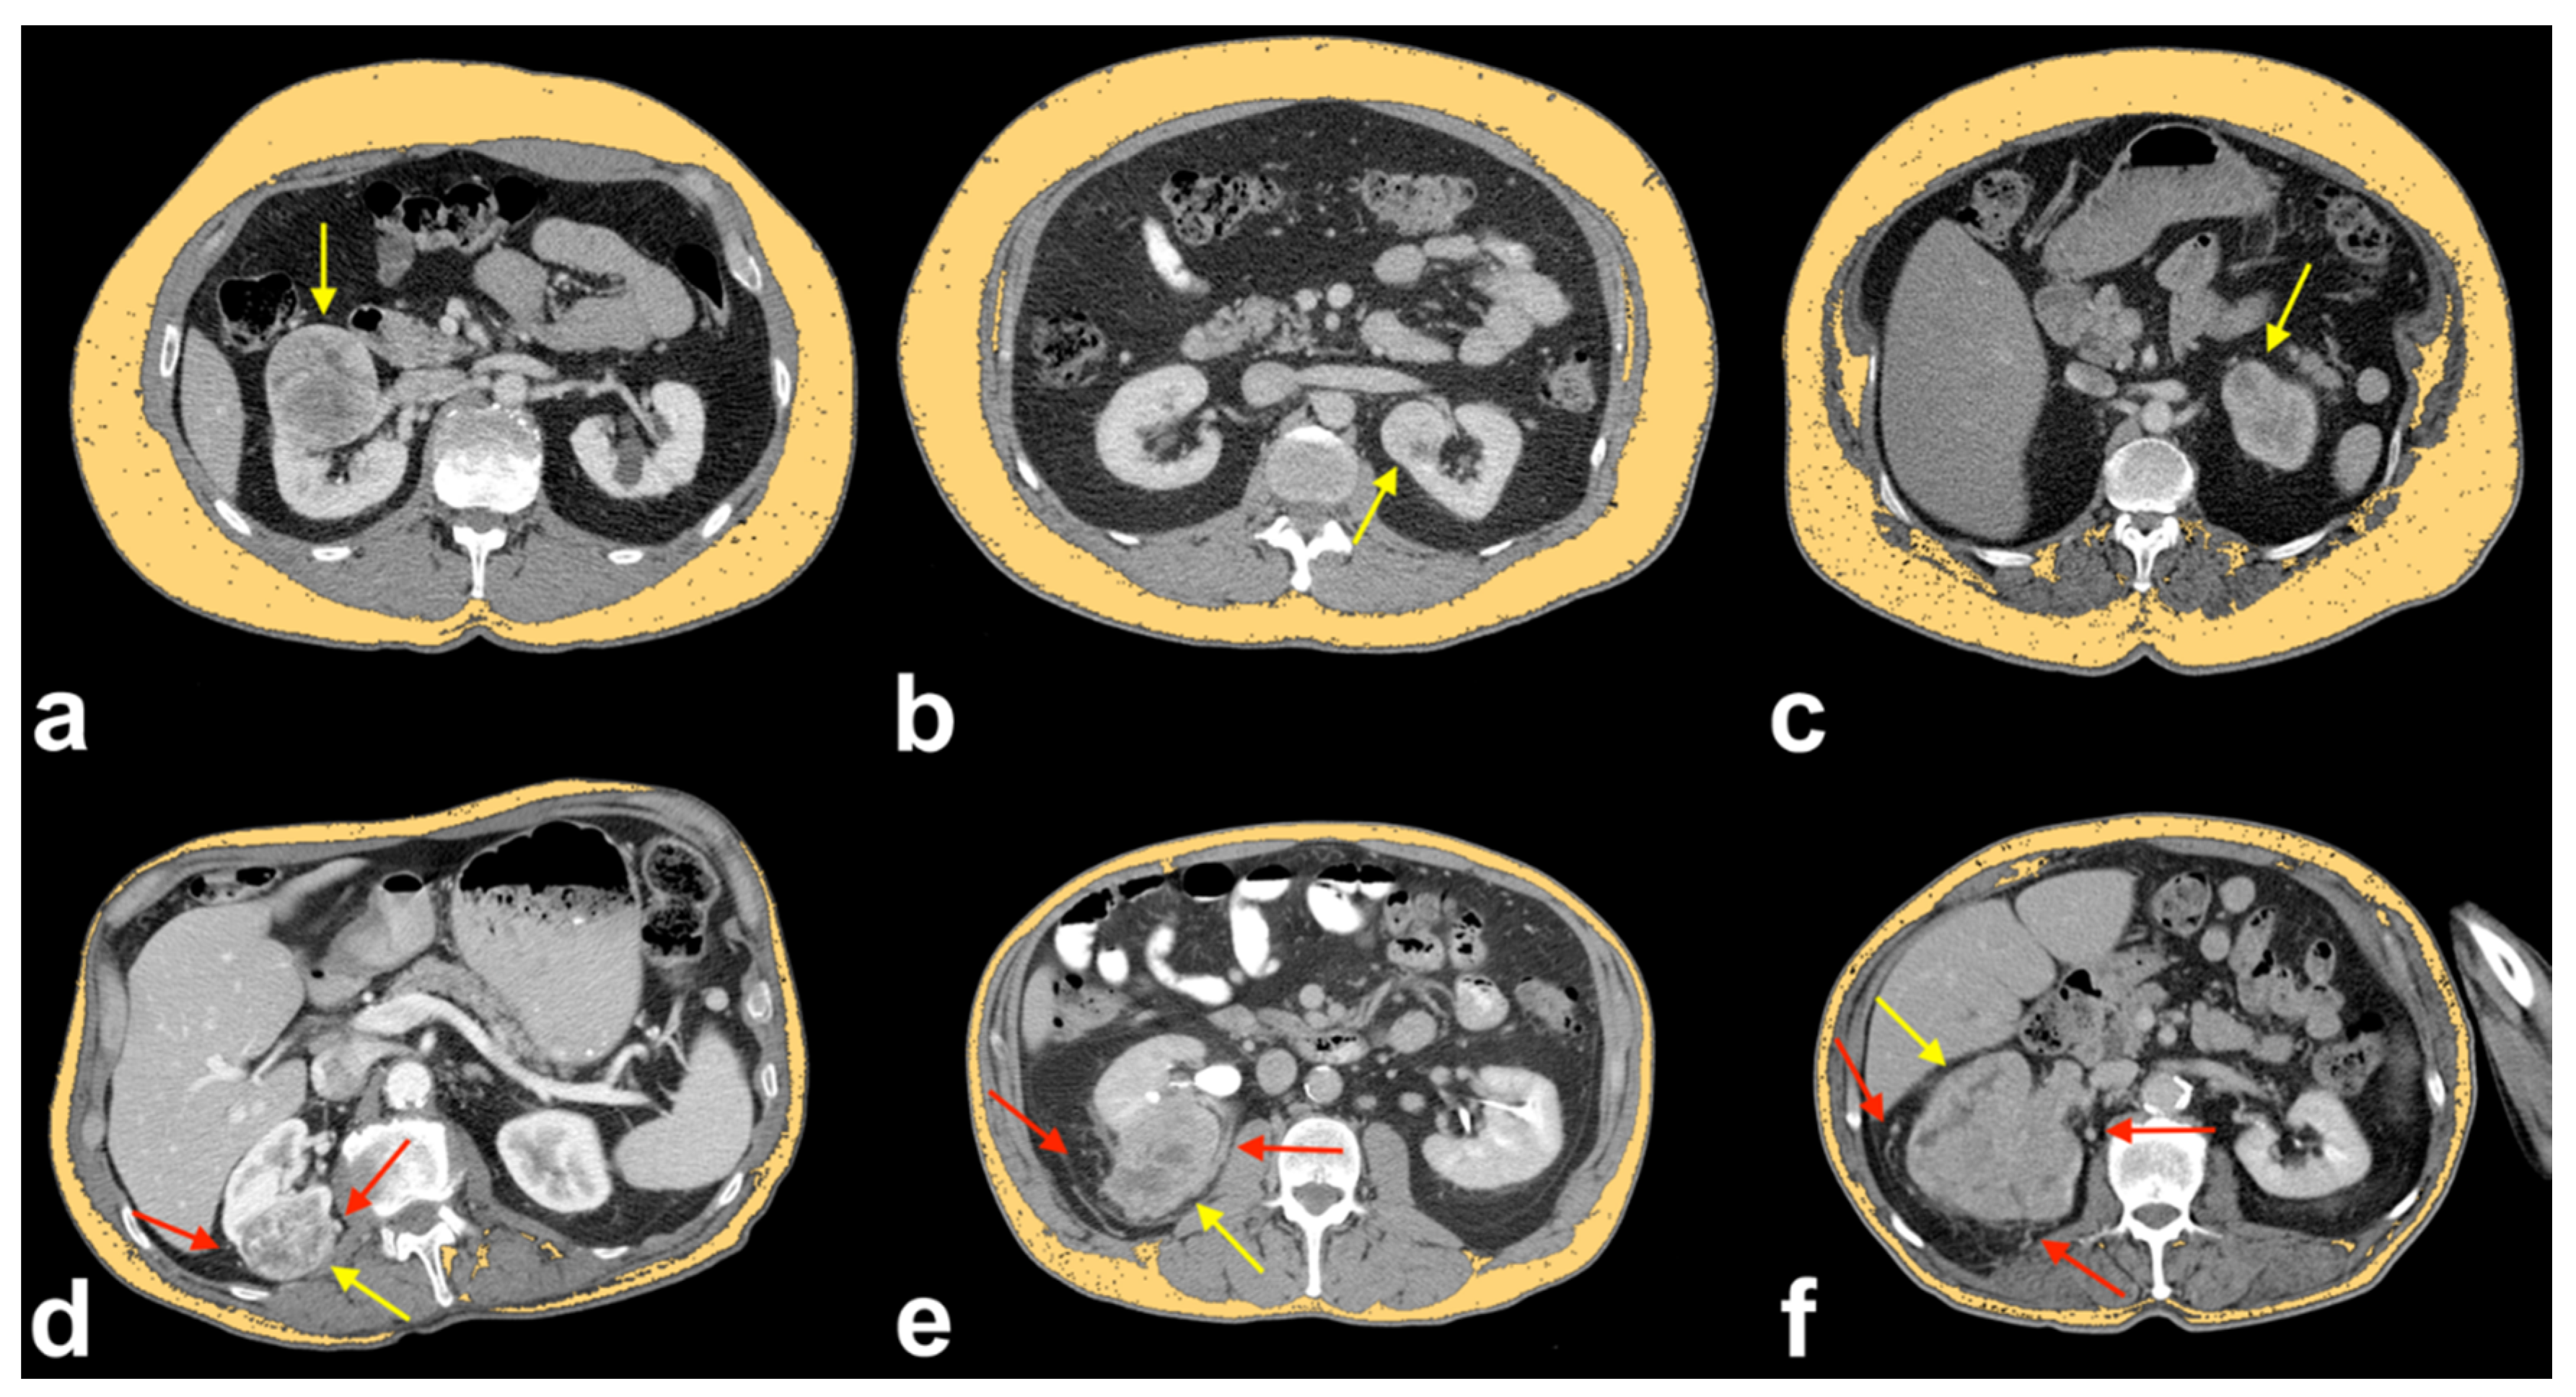

This cross-sectional observational study shows a significant decrease of SAT in ccRCCp patients compared to ccRCCa patients (Figure 3 and Figure 4).

Figure 4.

Axial CT images showing the orange ROIs of SAT areas in ccRCCa patients (a–c) and ccRCCp patients (d–f), the tumors in ccRCCa patients (yellow arrows in a–c) and ccRCCp patients (yellow arrows in d–f) and peritumoral collateral vessels in ccRCCp patients (red arrows in d–f). Note that there is a clear reduction of SAT in ccRCCp patients (d–f).